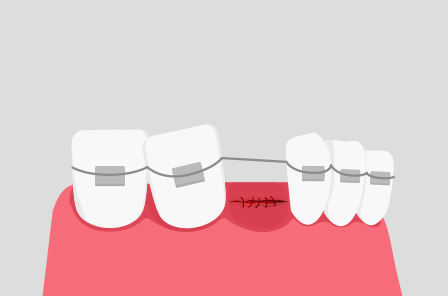

잇몸 봉합

발치 후 절개 부위를 봉합합니다.